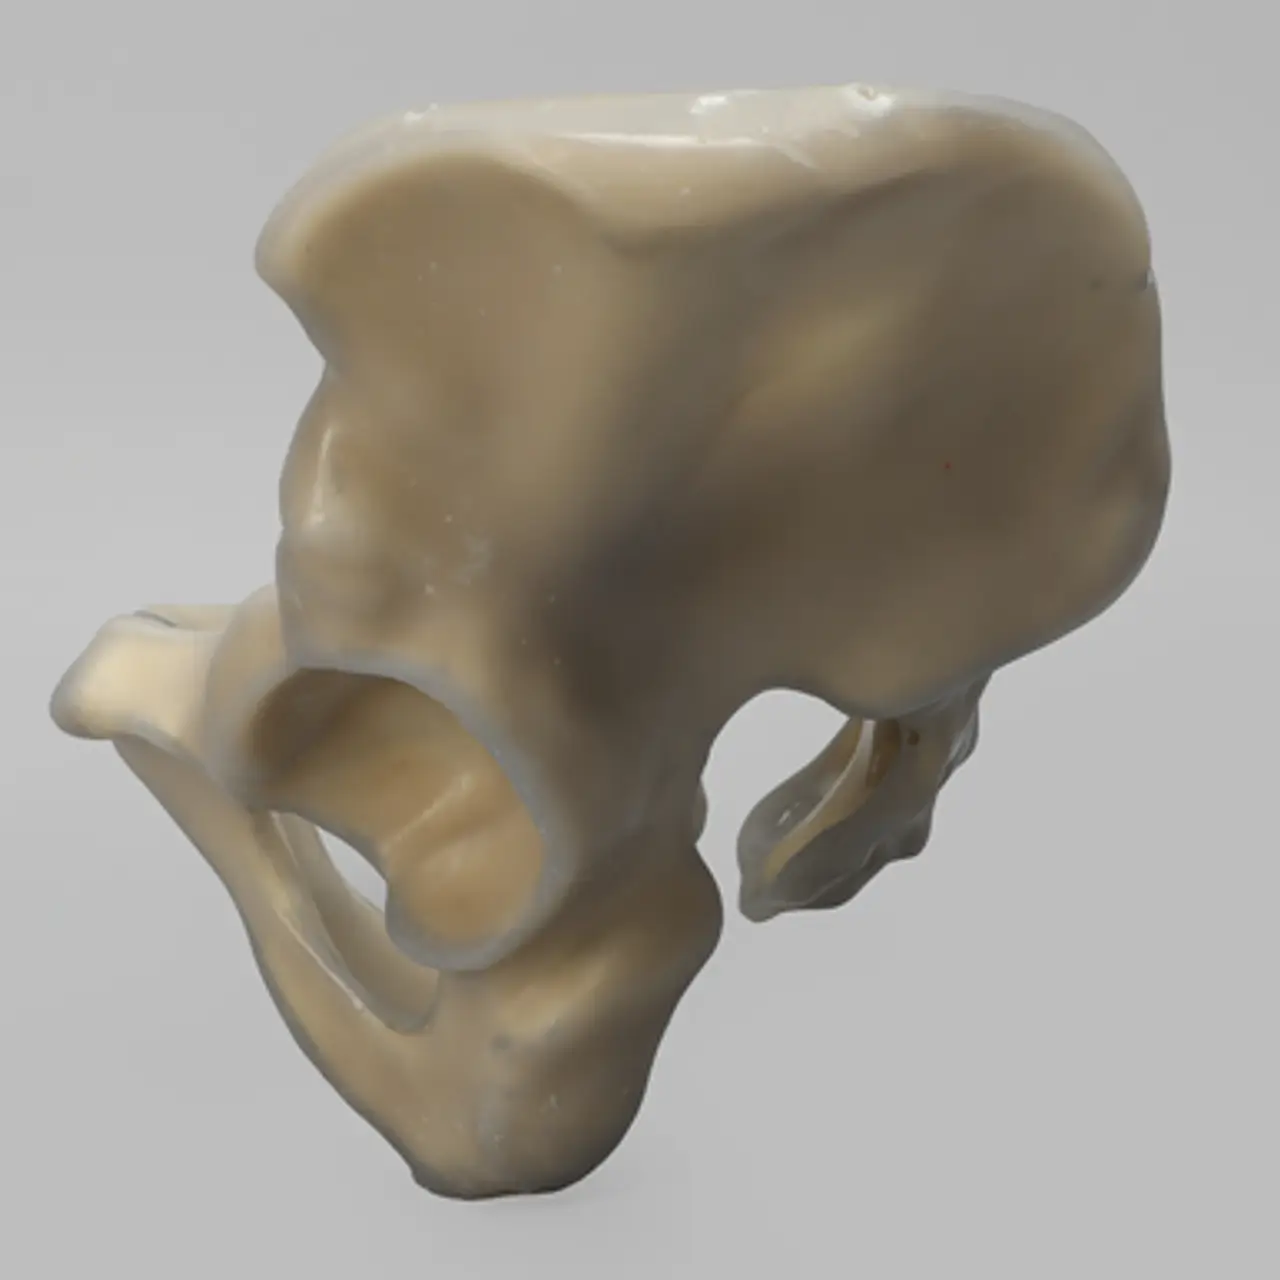

人工骨骨盆模型3415

人工骨模型,完整男性骨盆,absolute™ 第四代,17 PCF 实心泡沫芯,大号

用于力学测试的完整男性骨盆

我们的 absolute™ 骨模型 精确模拟人体骨骼的结构与力学特性,能够帮助科研人员和医疗器械企业在开发与审批过程中,轻松且经济地再现载荷与运动场景。该模型特别适用于生物力学研究、医疗器械测试及教学演示。

| 解剖部位 (Anatomy) | 骨盆 – 完整 |

| 模型类型 (Model Type) | absolute™ 骨模型 |

| 材料 (Material) | absolute™ |

| 尺寸 (Size) | 大号 |